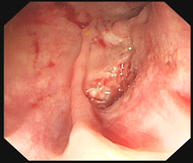

考虑直肠存在瘘口,遂再次行肠镜,肠镜检查除了发现回肠末端及结直肠多发溃疡,最重要的是发现直肠的确存在针尖样大小的瘘口(图3)。

图3  直肠内瘘口扩张前